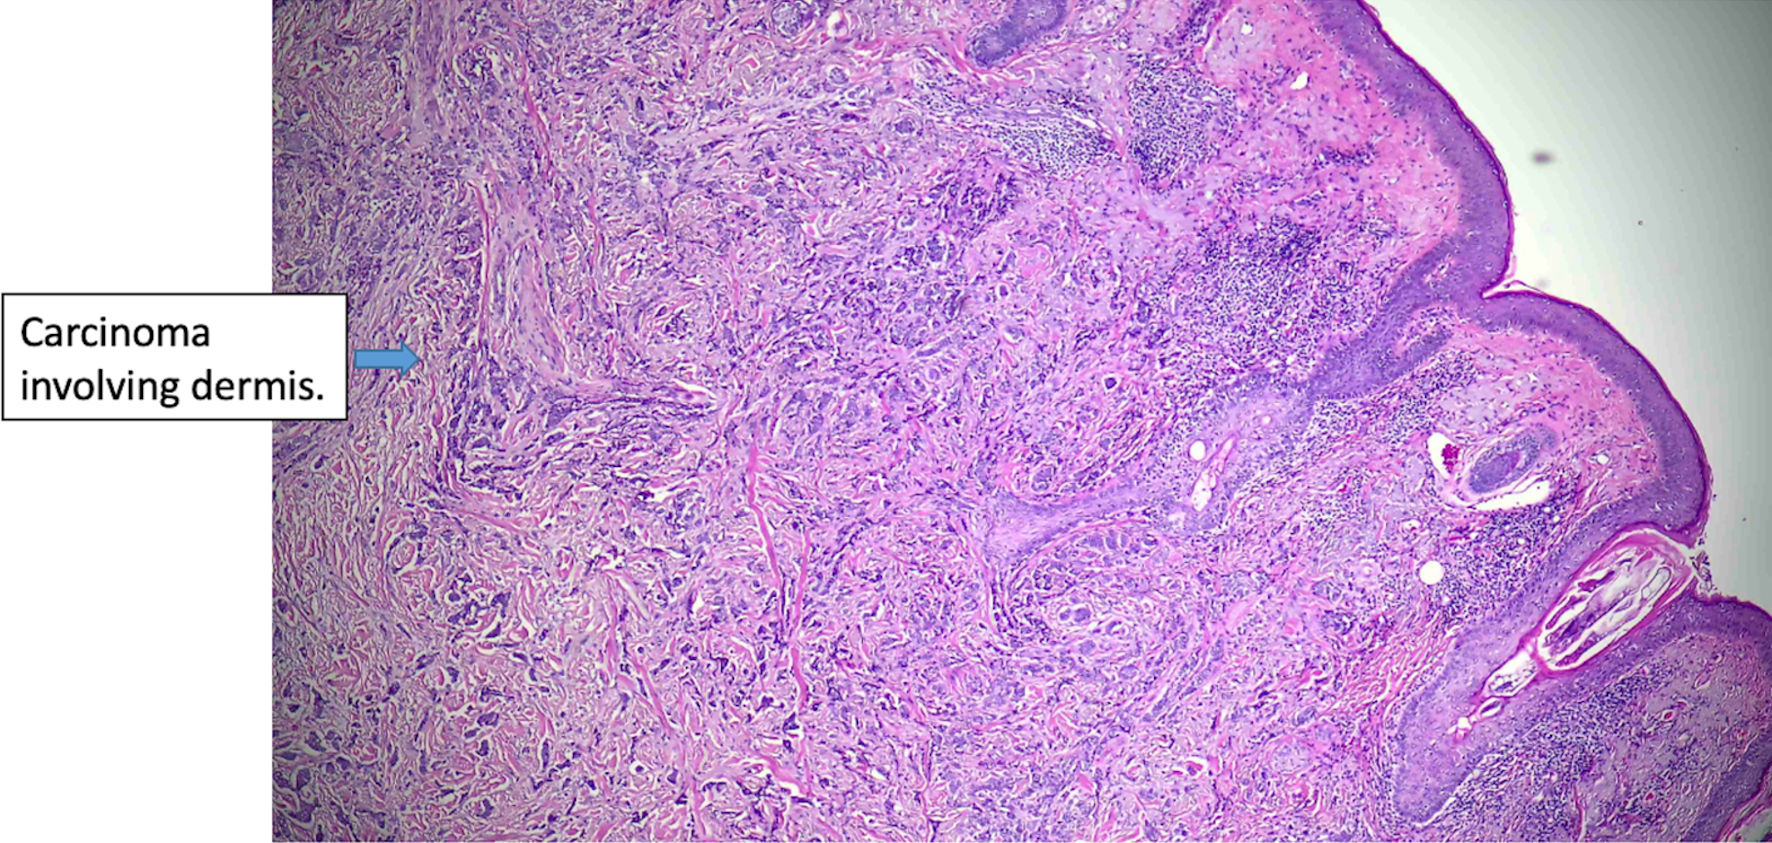

Click for large image

Figure 1. Histologic features of eccrine carcinoma at the initial diagnosis. Basaloid cells are infiltrating the dermis. (original magnification × 100).

The patient is a 66-year-old female who presented to our facility in 2024 with a recurrent left lower lip lesion characterized by throbbing pain and numbness. The lesion was initially found in 2017 and later recurred twice in 2020 and 2023, which was managed at another facility. The first surgery was done in 2017 with R0 resection. Pathology report of the recurrent lesion revealed invasive carcinoma, likely ductal carcinoma of the breast with neuroendocrine differentiation. Immunohistochemical stains were positive for CK7, GCDFP-15, mammaglobin, ER (99% strong), PR (99% strong), synaptophysin, and chromogranin, while negative for S100 and p63. E-cadherin showed a strong membranous pattern, suggestive of a ductal phenotype (Figs. 1-7). These findings indicated a primary ductal carcinoma of the breast. However, further investigation revealed no evidence of primary breast cancer. The recurrence of the lesion in 2020 led to another R0 resection, revealing a poorly differentiated carcinoma with potential neuroendocrine and sebaceous differentiation. The patient subsequently developed pain and contractures in the excision area, which prompted her to consult plastic surgery services in 2023, leading to lip reconstruction and another biopsy. This procedure resulted in an R2 resection, with the finding of poorly differentiated adenocarcinoma with extensive perineural invasion evident at the margins. Accessory breast tissue was carefully examined, but no trace of it was found in any of the slides. The pathology slides were originally obtained from the outside facility and reviewed by a dermatopathologist and breast-specialized pathologist. In their interpretation, in the absence of breast lesions, a diagnosis of eccrine carcinoma was considered more appropriate - a known diagnostic pitfall.